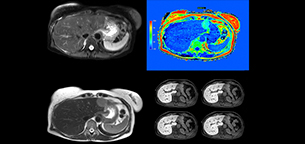

Dr. Kukuk’s liver exam begins with T2-weighted imaging, single shot and with fat suppression. “We always perform diffusion weighted imaging (DWI) with four b-values (0, 50, 250, 800) for lesion characterization, for monitoring after therapies, and for visualization of small lesions. Before giving contrast we routinely use the mDIXON Quant fat quantification sequence. Then we use dynamic e-THRIVE with an in-plane spatial resolution of 1.5 mm and high temporal resolution in just four breathholds of 13.1 seconds.” “Contrast enhancement is important to help us characterize lesions, for follow up in oncology patients and to inform clinicians when deciding on possible changes in the therapeutic regimen,” Dr. Kukuk explains. “Because we use liver-specific contrast agents we can obtain the T2-weighted images after the dynamic, to bridge the waiting time needed with these contrast agents. Just before the patient leaves the scanner we acquire another e-THRIVE in the axial plane and one or two coronals.”

“We have performed a study comparing mDIXON Quant fat percentages with results from histopathology. The correlation with different histologic methods was very good and also the correlation with MR spectroscopy was far above 0.9 – a nearly perfect correlation,” says Dr. Kukuk.

“Fatty liver disease is a common condition. Studies found a prevalence of non-alcoholic fatty liver disease in up to 44% in the general European population [1]. Liver fat cannot be quantified by ultrasound or CT, so biopsy has been the way to quantify fatty liver disease so far,” says Dr. Kukuk. “mDIXON Quant now allows non-invasive quantification of liver fat, which is valuable for both diagnosis and follow-up during dietary changes or therapy, for instance in hepatitis C.”

“The mDIXON Quant fat fraction maps provide quantitative information and also anatomical detail. The sequence is fast, usually taking about 16 seconds, which is just a breath hold for most patients. It definitely improves our efficiency.”